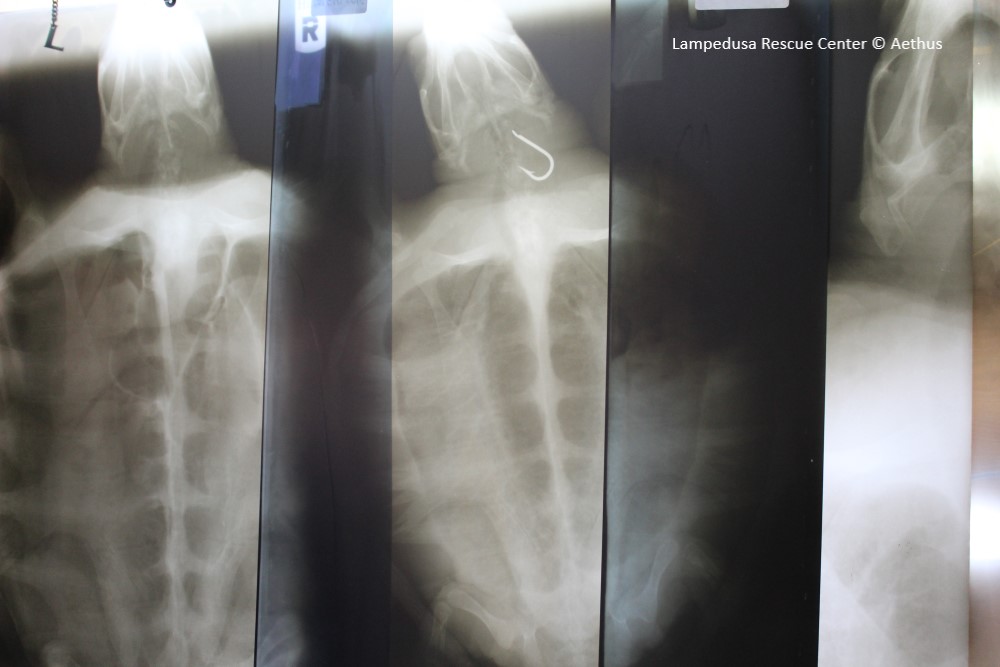

Diagnostic, XR, US and lab practices session (Dr Antonio Di Bello)